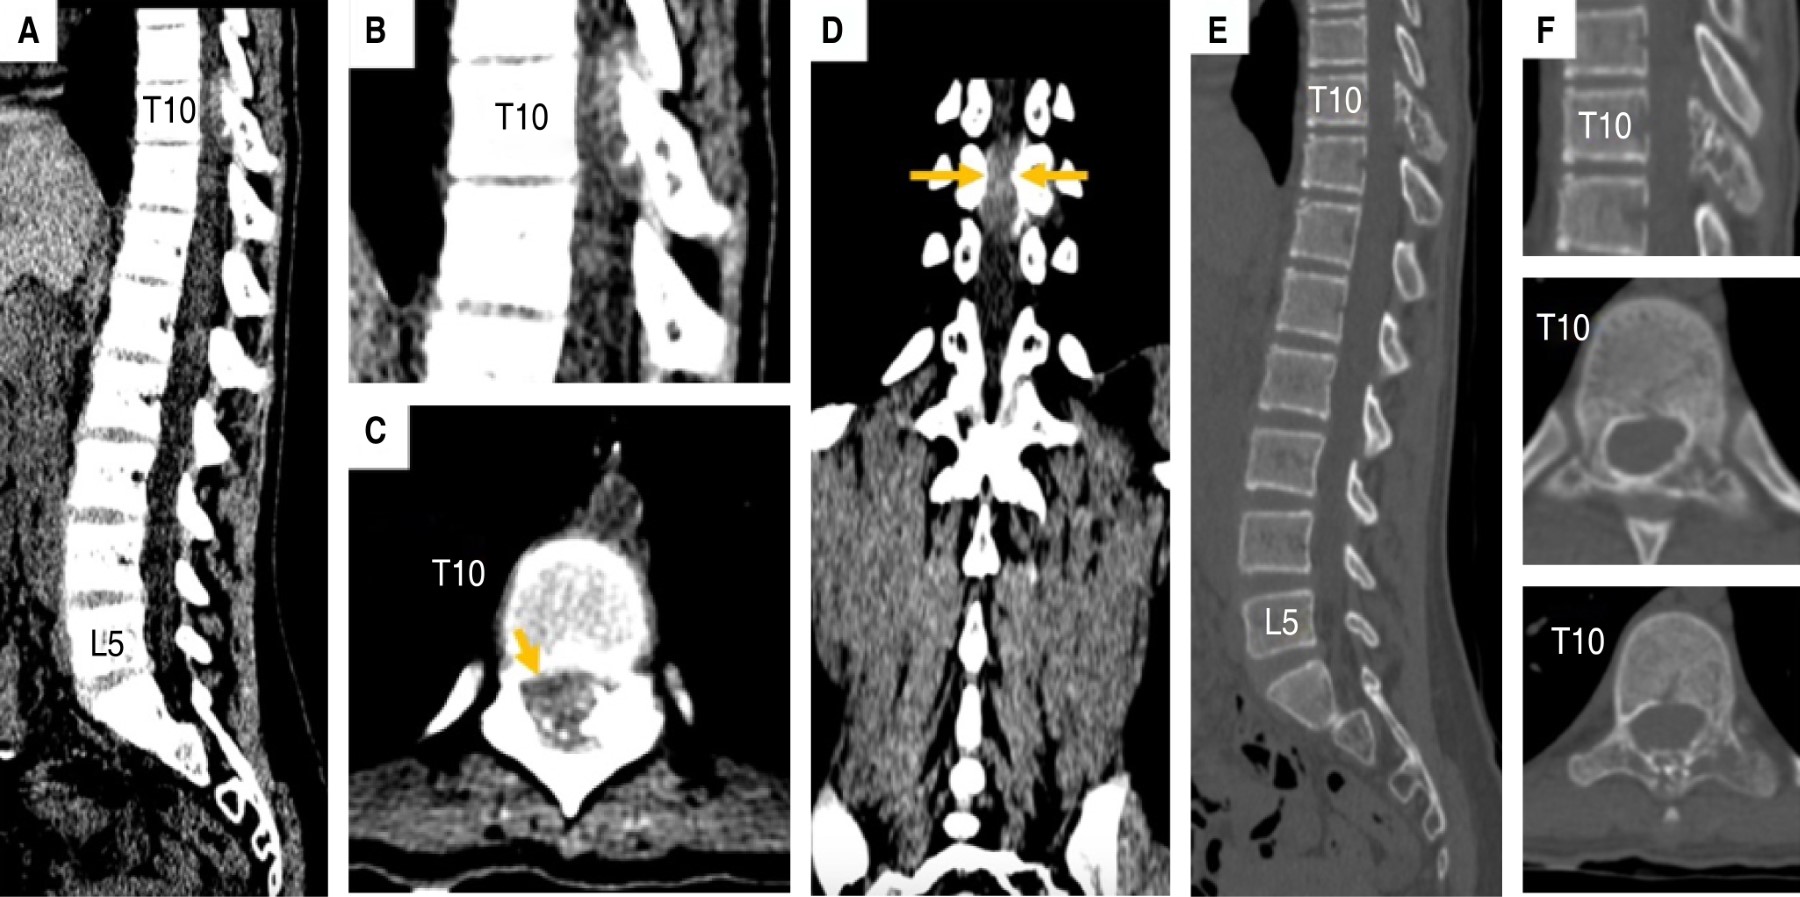

Figure 2